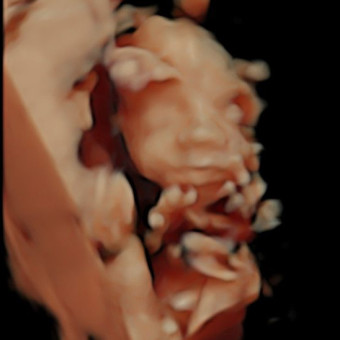

Amber & Cory Trusty

Eau Claire, WI

February 2026

Here comes the son! ☀️